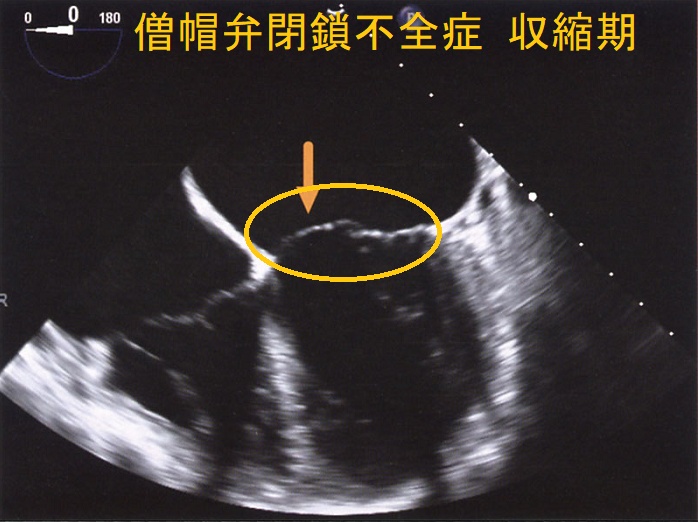

僧帽弁閉鎖不全症(MR)は、

- 僧帽弁逸脱:閉塞性肥大型心筋症、甲状腺機能亢進症の30%に起こる

自己免疫性に粘液多糖類が蓄積し、僧帽弁の粘液水腫性変化が生じます

- 甲状腺機能亢進症/バセドウ病の33%

- 甲状腺機能低下症/橋本病の36%

特に循環血液量・心拍出量が増加する甲状腺機能亢進症/バセドウ病では、僧帽弁腱索/乳頭筋断裂を引きおこす危険性が高い。(J Endocr Soc. 2018 Sep 17;2(11):1246-1250.)[Endocrinol Diabetes Metab Case Rep. 2022 Jul 1;2022:22-0298.]

僧帽弁腱索/乳頭筋断裂がなく、粘液腫性変性による中等度から重度の僧帽弁閉鎖不全症(MR)なら、甲状腺機能の正常化に伴い改善する可能性があります。[BMJ Case Rep. 2021 Feb 4;14(2):e239626.]